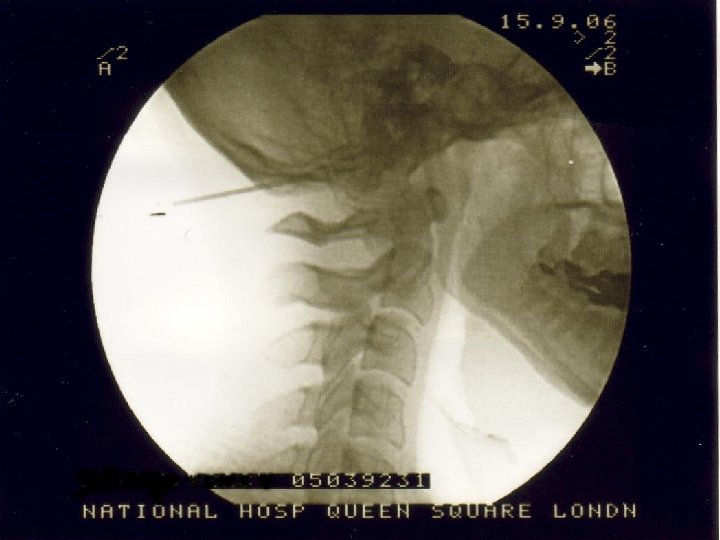

Stages of the operation n Insertion of electrodes « LA n + Sedation Test stimulation of electrodes « Awake n Insertion of battery and tunnelling of leads « Asleep n n (GA with LMA) Alternatively GA throughout if difficult airway or reflux USA: 2 stage procedure

Skin marking n n n Awake, sitting upright on stool Midline Intermastoid line Spinous process of C 1 3 cm from midline Chosen position of battery

Positioning n n Lateral position Access to all operative areas Strict aseptic technique to establish field Anaesthetist access to patient for communication and airway

Test stimulation n n Radiating occipital paraesthesiae bilaterally 300 microseconds pulse width 60 -80 Hz At low amplitude – typically 1 -2 V If no paraesthesiae or if amplitude >4 V then reposition electrode